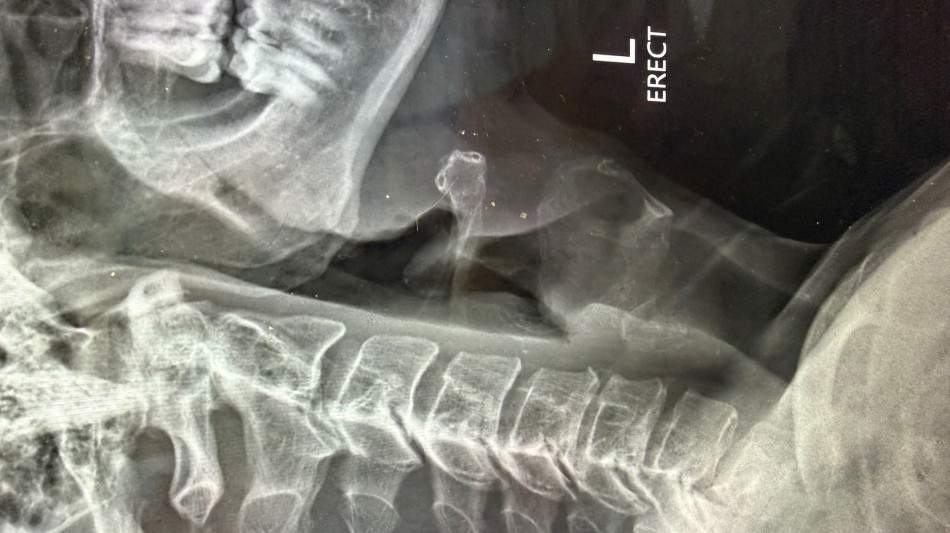

The patient, a 47-year-old man, presented with progressive neck pain, arm pain, and weakness in the setting of spinal cord compression and severe nerve root compression with associated bone spur formation. After failing conservative management, the patient was taken to surgery for a three-level cervical disc replacement to decompress the spinal cord, relieve nerve compression, and remove osteophytic pathology.

The Synergy Disc® is a motion-preserving artificial cervical disc developed by Synergy Spine Solutions and engineered with a lordotic polyethylene core designed to maintain and restore physiologic alignment while allowing controlled motion. The Synergy Disc® is the only artificial cervical disc currently available that combines motion preservation with intentional alignment correction in a single device. The device recently demonstrated superiority to anterior cervical discectomy and fusion (ACDF) in a U.S. Investigational Device Exemption (IDE) clinical trial.